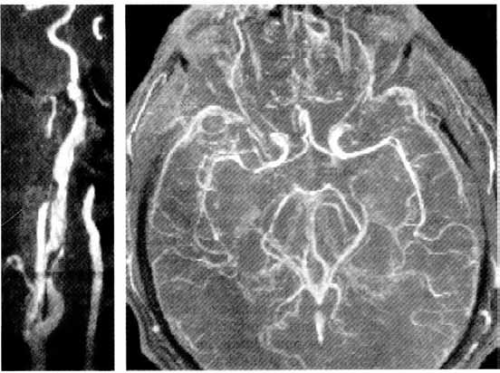

MRI arteriografija:

Levo: stenoza ekstrakranijalnog dela unutrašnje karotidne arterije koja se ne može dovoljno precizno definisati. Desno: stenoza srednje cerebralne arterije.